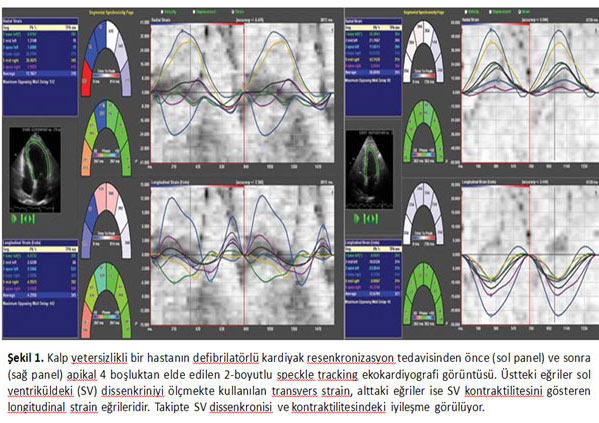

Sol ventrikülün mekanik dissenkronisi, apikal 4- ve 2-boşluk görüntülerinden 12 anatomik segment boyunca sistol esnasında bölgesel pik transvers straine karşılık gelen zamanın standart sapması olarak belirlendi (msn) (Şekil 1). Global longitudinal strain SV kontraktil işlevinin detaylı bir ölçüm yöntemidir ve apikal 4- ve 2- boşluk görüntülerinden 12 anatomik segment boyunca pik longitudinal strain’in ortalamasıyla elde edildi (%).

Hastalara EF ve SV volümlerini içeren standart eko incelemesi yapıldı. Ardından B-mod STE ile SV dissenkronisi ve kontraktilitesi değerlendirildi.

Bu yöntem, kalp içindeki çoklu referans noktalarını izleyerek kardiyak hareketi tanımlar. Bu yöntemle longitudinal, sirkumferansiyel, radial/tranvers yönlerdeki harekete ait veriler elde edilir. Bilinen Doppler ve doku Doppler incelemelerinden farklı olarak açı bağımlı değildir ve pasif hareket ile aktif kontraksiyonu birbirinden ayırt edebilir.